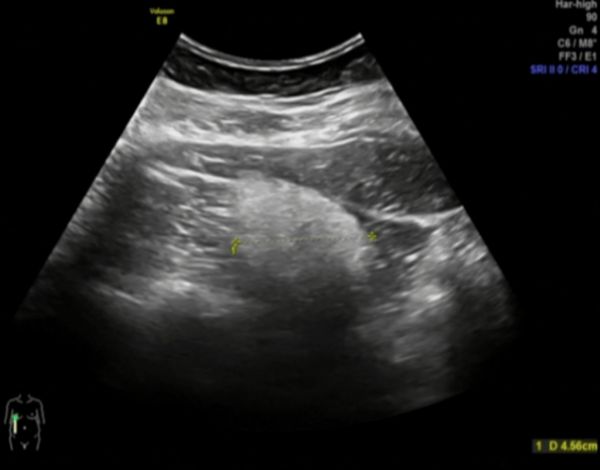

术前超声检查

李女士入院后常规完善检查,术前评估右侧肾错构瘤具备保肾条件,左侧肾错构瘤尚小,可以先定期随访观察。由泌尿外科专家褚靖副院长、郑明康主任团队为李女士行腹腔镜下右肾错构切除术(保肾手术),手术非常成功。术后李女士如期康复出院。近期复查超声提示右肾大小正常、肾实质均匀,恢复良好。